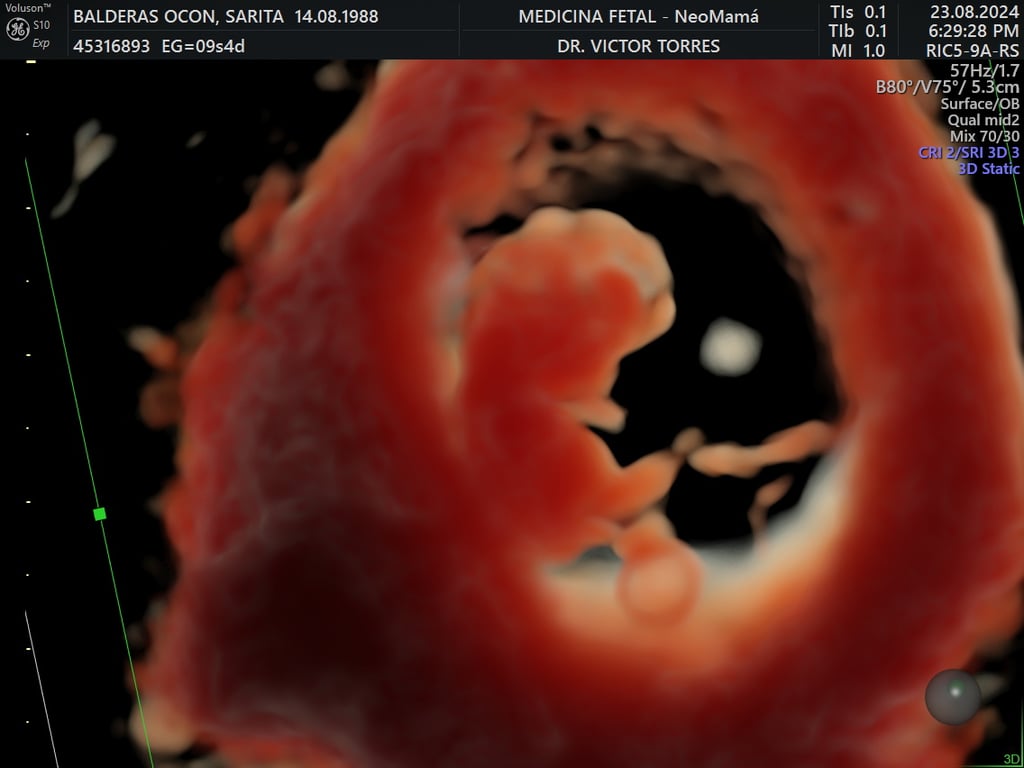

ecografía de viabilidad

4 - 11 semanas